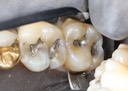

Ted Kanamori #30 pre-op

Ted Kanamori #31 caries removal

Ted Kanamori #31 prep